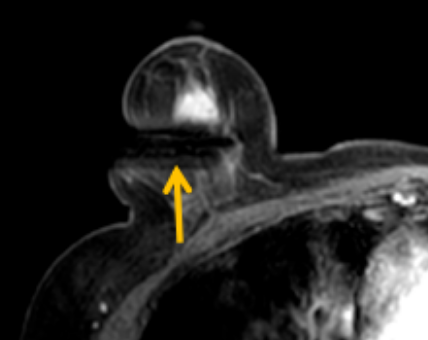

陳寶瑩評估圖像后發(fā)現(xiàn)病變?yōu)閮H僅在磁共振增強時顯示,為非腫塊樣病變,比較散,必須取得足夠多的組織才能確保病理檢查的準(zhǔn)確性,常用的核芯針活檢獲取的組織較少,因此最終確定了磁共振引導(dǎo)下行真空輔助抽吸旋切活檢。取得患者及家屬認(rèn)可后,陳寶瑩帶領(lǐng)團隊開始進行術(shù)前準(zhǔn)備。

針對患者乳房小固定難度大這一問題,陳寶瑩通過巧妙體位和固定器的調(diào)整,順利固定好乳房。經(jīng)過磁共振多模態(tài)掃描,陳寶瑩找出病變活性成分相對集中區(qū)域,精準(zhǔn)確定穿刺路徑,置入引導(dǎo)針、旋切針,到位后多角度旋切取出足量組織,拔除旋切針后即時行磁共振掃描,精準(zhǔn)取得組織且術(shù)區(qū)出血很少,遂加壓包扎,整個過程非常順利,旋切活檢后患者回家休息。兩天后隨訪,李女士沒有任何不適,五天后皮膚上幾毫米的小切口已經(jīng)愈合。最終病理結(jié)果證實為乳腺導(dǎo)管原位癌,為早期乳腺癌,為患者后續(xù)針對性治療奠定了基礎(chǔ)。